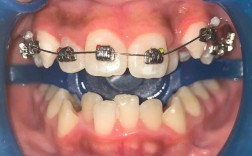

颌间牵引是通过连接上下颌牙齿的牵引装置,纠正上下颌牙弓及颌骨间的位置关系,常用于Ⅱ类、Ⅲ类错畸形的矫正,其图片特征表现为:

- 咬合关系动态:口内正面或咬合面图片中,可见上下颌牙齿通过橡皮圈(如“Ⅲ类牵引”“Ⅱ类牵引”)连接,类牵引时,橡皮圈一端挂在上颌第一磨牙颊面管,另一端挂于下颌尖牙托槽,图片可清晰显示下颌尖牙向近中、上颌磨牙向远中的移动趋势;

- 中线对齐情况:正面张口位图片可观察上下颌中线是否对齐,对于偏颌畸形患者,牵引过程中图片显示中线逐渐居中,面部不对称得到纠正。